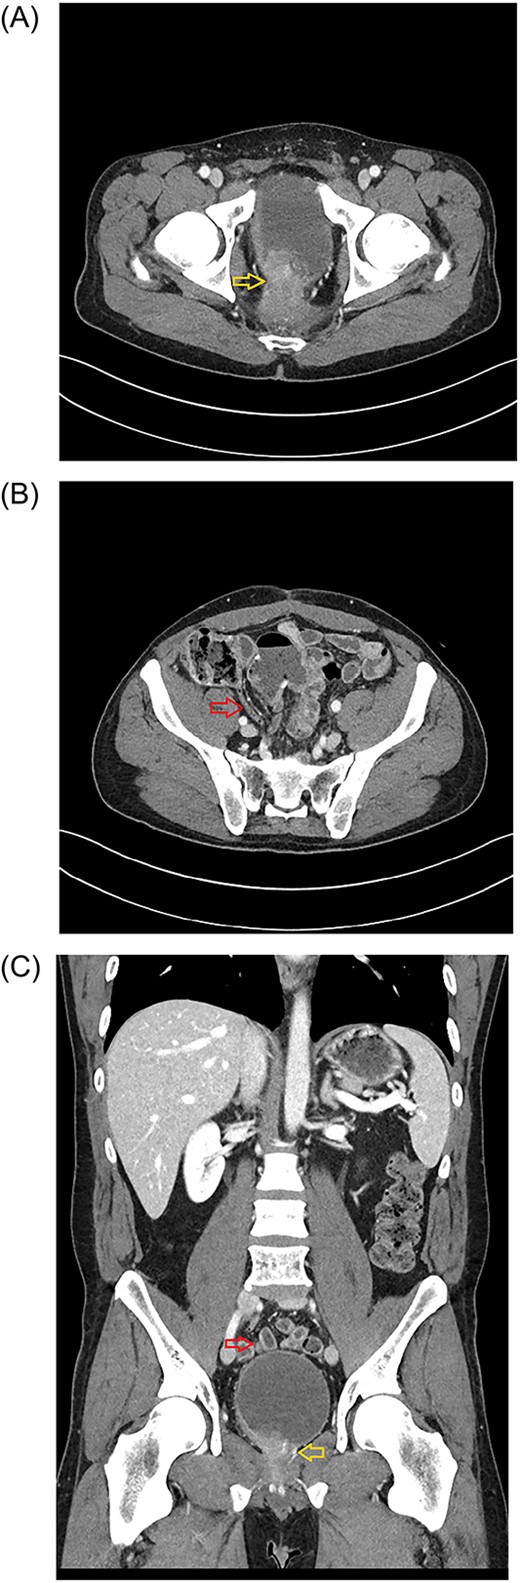

Axial plane of the abdominopelvic CT scan (January 2023) showing the tumor invading bladder (yellow arrow) (A) and the pelvic location of the appendix (red arrow) (B). Abdominal CT scan (Coronal plane) (C) showing the tip of appendix (upper, red arrow) and tumor invading bladder (lower, yellow arrow).

The first stage included a posterior subtotal sacrectomy plus neurectomy of pudendal nerves and neuroplasty of both sciatic nerves. An interval recovery of 24 hours was allowed. The second stage included complete exenteration including bladder and prostate, completion of subtotal sacrectomy, ventral rectus abdominus myocutaneous flap reconstructive surgery to fill the pelvic defect, creation of an ileal conduit and delivery of IORT. During the abdominal portion of the case, prophylactic appendectomy of a benign appearing appendix was done because his anatomy was such that the appendix naturally resided in the pelvis (Fig. 1B and C) and the operative surgeon wanted to avoid need for future appendectomy in a multiply reoperative and irradiated pelvic-exenteration field. His postoperative clinical course was difficult, which was expected for this type of surgery including need for transfusion, urinary tract infection, posterior wound dehiscence, pelvic abscess requiring drainage, and neuropathic leg pain accompanied by foot drop. He has had a slow but steady recovery from the extensive surgery. Unexpectedly, definitive pathology reported appendix with GN at the distal tip (Figs 2 and 3). Given the incidental nature of this finding, preoperative imaging was reviewed. CT scans showed normal appendix without apparent mass (Fig 1B and C).